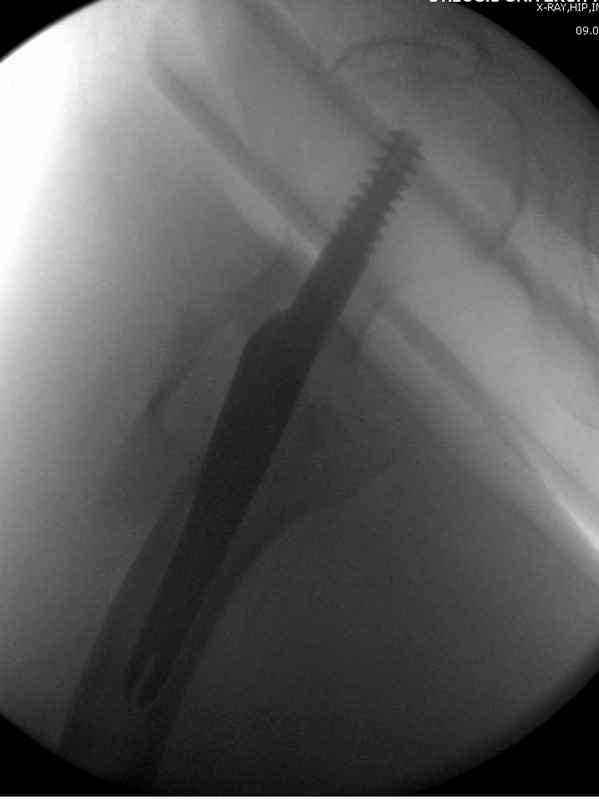

Здесь пара случаев фиксации похожих переломов:

первый высокоэнергетическая травма 36 лет

Djoldas Kuldjanov, M.D.

Department of Orthopedic Surgery

St. Louis University